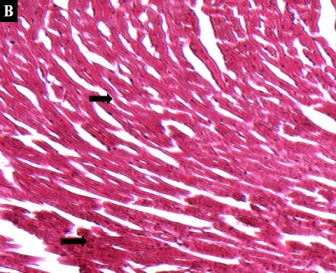

The cardiac tissues of control mice showed normal organization of cardiac muscle fibers surrounded by an endomysium of delicate connective tissue with rich capillary network (Fig-3A). Administration of the krait venom induced variable degrees histopathological alterations in cardiac tissues as heart-hemorrhage, multifocal areas of myocardial fiber and separation of the muscle fibers which appeared to contain separate myofibrils (fig-3B).

Fig. 3: (A) The image from control cardiac muscle showing normal and compact configuration. (B) Whereas, the heart section of envenomated mice showing a range histological alterations as heart-hemorrhage (arrow headed), multifocal areas of myocardial fiber and separation of the muscle fibers (arrow headed)